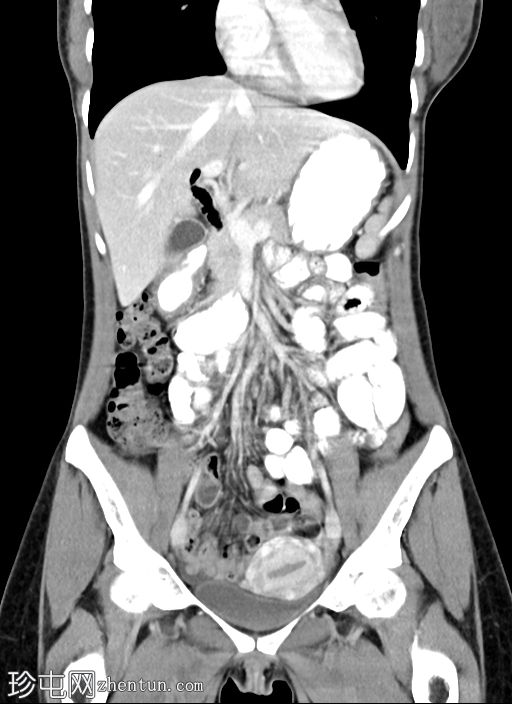

冠状位增强扫描(门静脉期)

肝外胆管、肝内胆管及胆囊内可见气体。后续增强(静脉)检查中加用口服造影剂,结果显示造影剂从十二指肠反流至胆总管,最终进入胆囊。

幽门成形术和迷走神经切断术史可能解释奥迪氏括约肌功能障碍,导致气体和口服造影剂反流至胆道系统。目前有几种关于迷走神经干切断术后奥迪氏括约肌功能障碍的可能机制;该手术会改变括约肌的压力和运动能力。